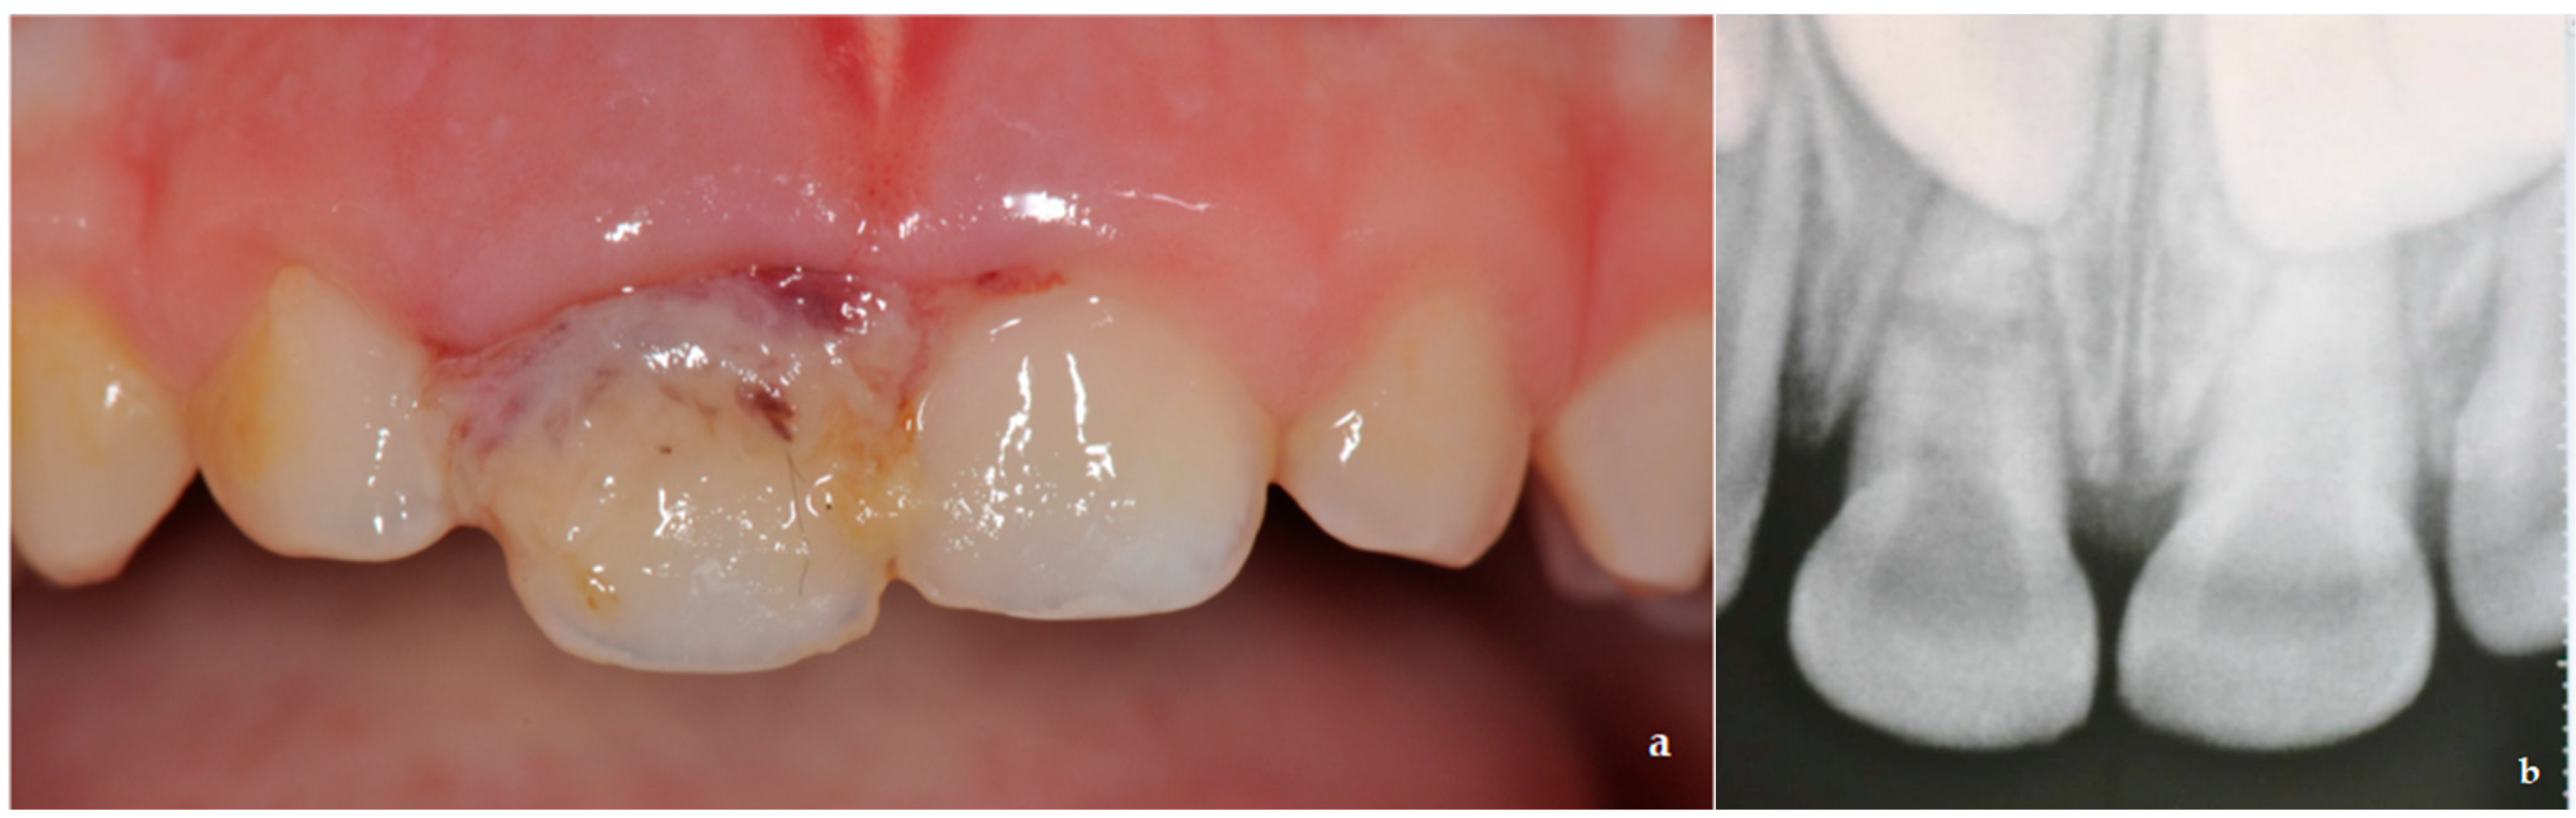

Singlevisit pulpectomy in a primary lower molar. a Clinical Root Canal Irrigants In Primary Teeth Root canal irrigants, sodium hypochlorite, chlorhexidine, chelating agents, plant extracts. This chapter highlights about the efficacy of different root canal irrigants in primary teeth. The most prevalent bacterial species in infected root canals of primary teeth have been found to be enterococcus faecalis, porphyromonas. Onçag o, cogulu d, uzel a. For teeth with vital pulp where the root canals are. Root Canal Irrigants In Primary Teeth.